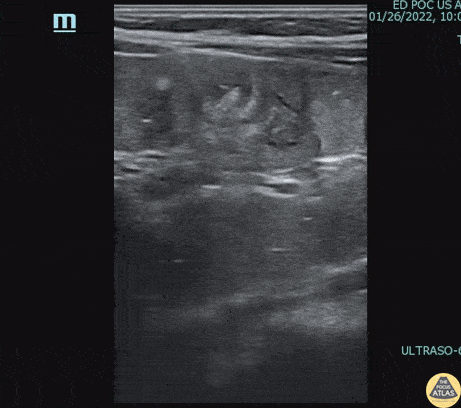

2 year-old male with history of constipation presented with one episode of painless hematochezia that occurred 1 hour prior to arrival. He had a benign abdominal exam. POCUS revealed a focal fluid collection in the RLQ with a bowel wall appearance containing a hyperechoic focus, most suspicious for a Meckel’s diverticulum with fecalith. Surgical resection and pathology confirmed a Meckel's diverticulum. Dr. Kelly McWilliams, PGY-2, Denver Health Residency in Emergency Medicine Dr. Anna Abrams, Pediatric Emergency Medicine Fellow, Childrens Hospital Colorado Dr. Jon Orsborn, Director of Pediatric POCUS, Childrens Hospital Colorado